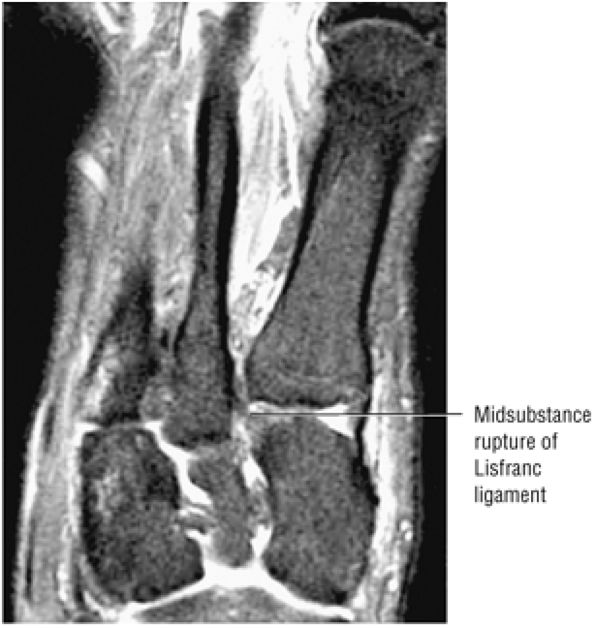

FIGURE 5.27 ● Axial anatomy of the ankle and foot. (A) The flexor digitorum longus, flexor hallucis longus, peroneus brevis, soleus, and extensor digitorum muscles are examined at this level for strain, tears, or fatty atrophy that may suggest denervation. (B) The tibialis anterior, extensor hallucis longus, and extensor digitorum longus tendons are examined on every ankle MR examination. Extensor tendon pathology is frequently overlooked if these tendons are not included as part of the ankle checklist. (C) Tears and sprains of the anterior syndesmotic ligament are a frequent cause of persistent ankle pain following ankle sprain. The syndesmotic ligaments are thick, tough ligaments that are important ankle stabilizers, and delayed diagnosis of syndesmotic tears may result in significant degenerative arthrosis at the tibiotalar joint due to the resulting ankle instability. The syndesmotic ligaments course obliquely inferiorly from the tibia to the fibula and are not usually visualized in their entirety on a single axial image; rather, their course is followed on at least two or three successive axial images. (D) The peripheral margin of the peroneal tendons and tibialis posterior tendon should normally never extend beyond the peripheral margins of the lateral and medial malleoli, respectively. Tendon subluxation around the posterior corner of either malleolus is indicative of a tear of the overlying flexor retinaculum (medially) or peroneal retinaculum (laterally). When the retinacula are torn, the tendon is free to intermittently sublux or dislocate, leading to tendon degeneration, pain, and tendon dysfunction. (E) Suspected osteochondral lesions of the talar dome are visualized and further characterized on axial images through the top of the talar dome. (F) The peroneus brevis tendon may normally appear somewhat flattened. However, as the tendon degenerates, it becomes U-shaped and drapes around the anterior aspect of the peroneus longus and becomes impinged between the peroneus longus tendon and the lateral malleolus. With further degeneration, the peroneus brevis may split or completely rupture. (G) Evidence of anterior talofibular ligament injury is visualized on the majority of MR ankle examinations and appears as thickening, intermediate signal with ill-defined fibers, or attenuation of the ligament. This is commonly asymptomatic. (H) Because the flexor hallucis longus tendon sheath communicates with the tibiotalar joint, fluid may normally be present within the tendon sheath in proportion to the amount of fluid in the tibiotalar joint. If there is fluid within the tendon sheath out of proportion to that seen in the tibiotalar joint, tenosynovitis is most likely present. The finding of flexor hallucis longus tenosynovitis should prompt a search for an os trigonum, as impingement of the flexor hallucis longus tendon between an os trigonum and the posterior tibial plafond is a common cause for FHL tenosynovitis. (I) The calcaneofibular ligament (CFL) passes anterior and medial to the peroneal tendons. On the image at which the CFL passes directly medial to the peroneus brevis tendon, the appearance of the peroneus brevis and the CFL side by side is occasionally mistaken for a split peroneus brevis tendon. (J) Dilated posterior tibial veins within the tarsal tunnel occasionally compresses the tibial nerve. In the setting of clinical suspicion for tarsal tunnel syndrome or if there is evidence of muscle denervation on MR images, the size of the posterior tibial veins should be described. (K) The spring ligament is identified at this axial image location, extending from the anteromedial calcaneus to the posteromedial navicular. Tears of the spring ligament may result in medial instability and hindfoot valgus. (L) The posterior tibialis tendon (PTT) may normally become thickened and fan-like as it passes posterior to its navicular insertion (prior to also inserting on the cuneiforms and the base of the second through fourth metatarsals). In the absence of other findings, the thickening of the PTT at this level should not be mistaken for focal tendinosis. (M) On inferior images through the ankle, Lisfranc's ligament is occasionally included in the FOV. Lisfranc's ligament extends from the medial cuneiform to the base of the second metatarsal. If Lisfranc's ligament is included in the FOV, the status of the ligament should be described, as undiagnosed Lisfranc ligament tears can lead to debilitating midfoot arthrosis. (N) As the medial and lateral tendons turn from their vertical course to a horizontal course along the plantar aspect of the foot, the tendons may demonstrate a magic-angle artifact, causing the tendons to appear gray on short-TE images, mimicking tendinosis. Correlation with images using longer TE values is advised in such situations.